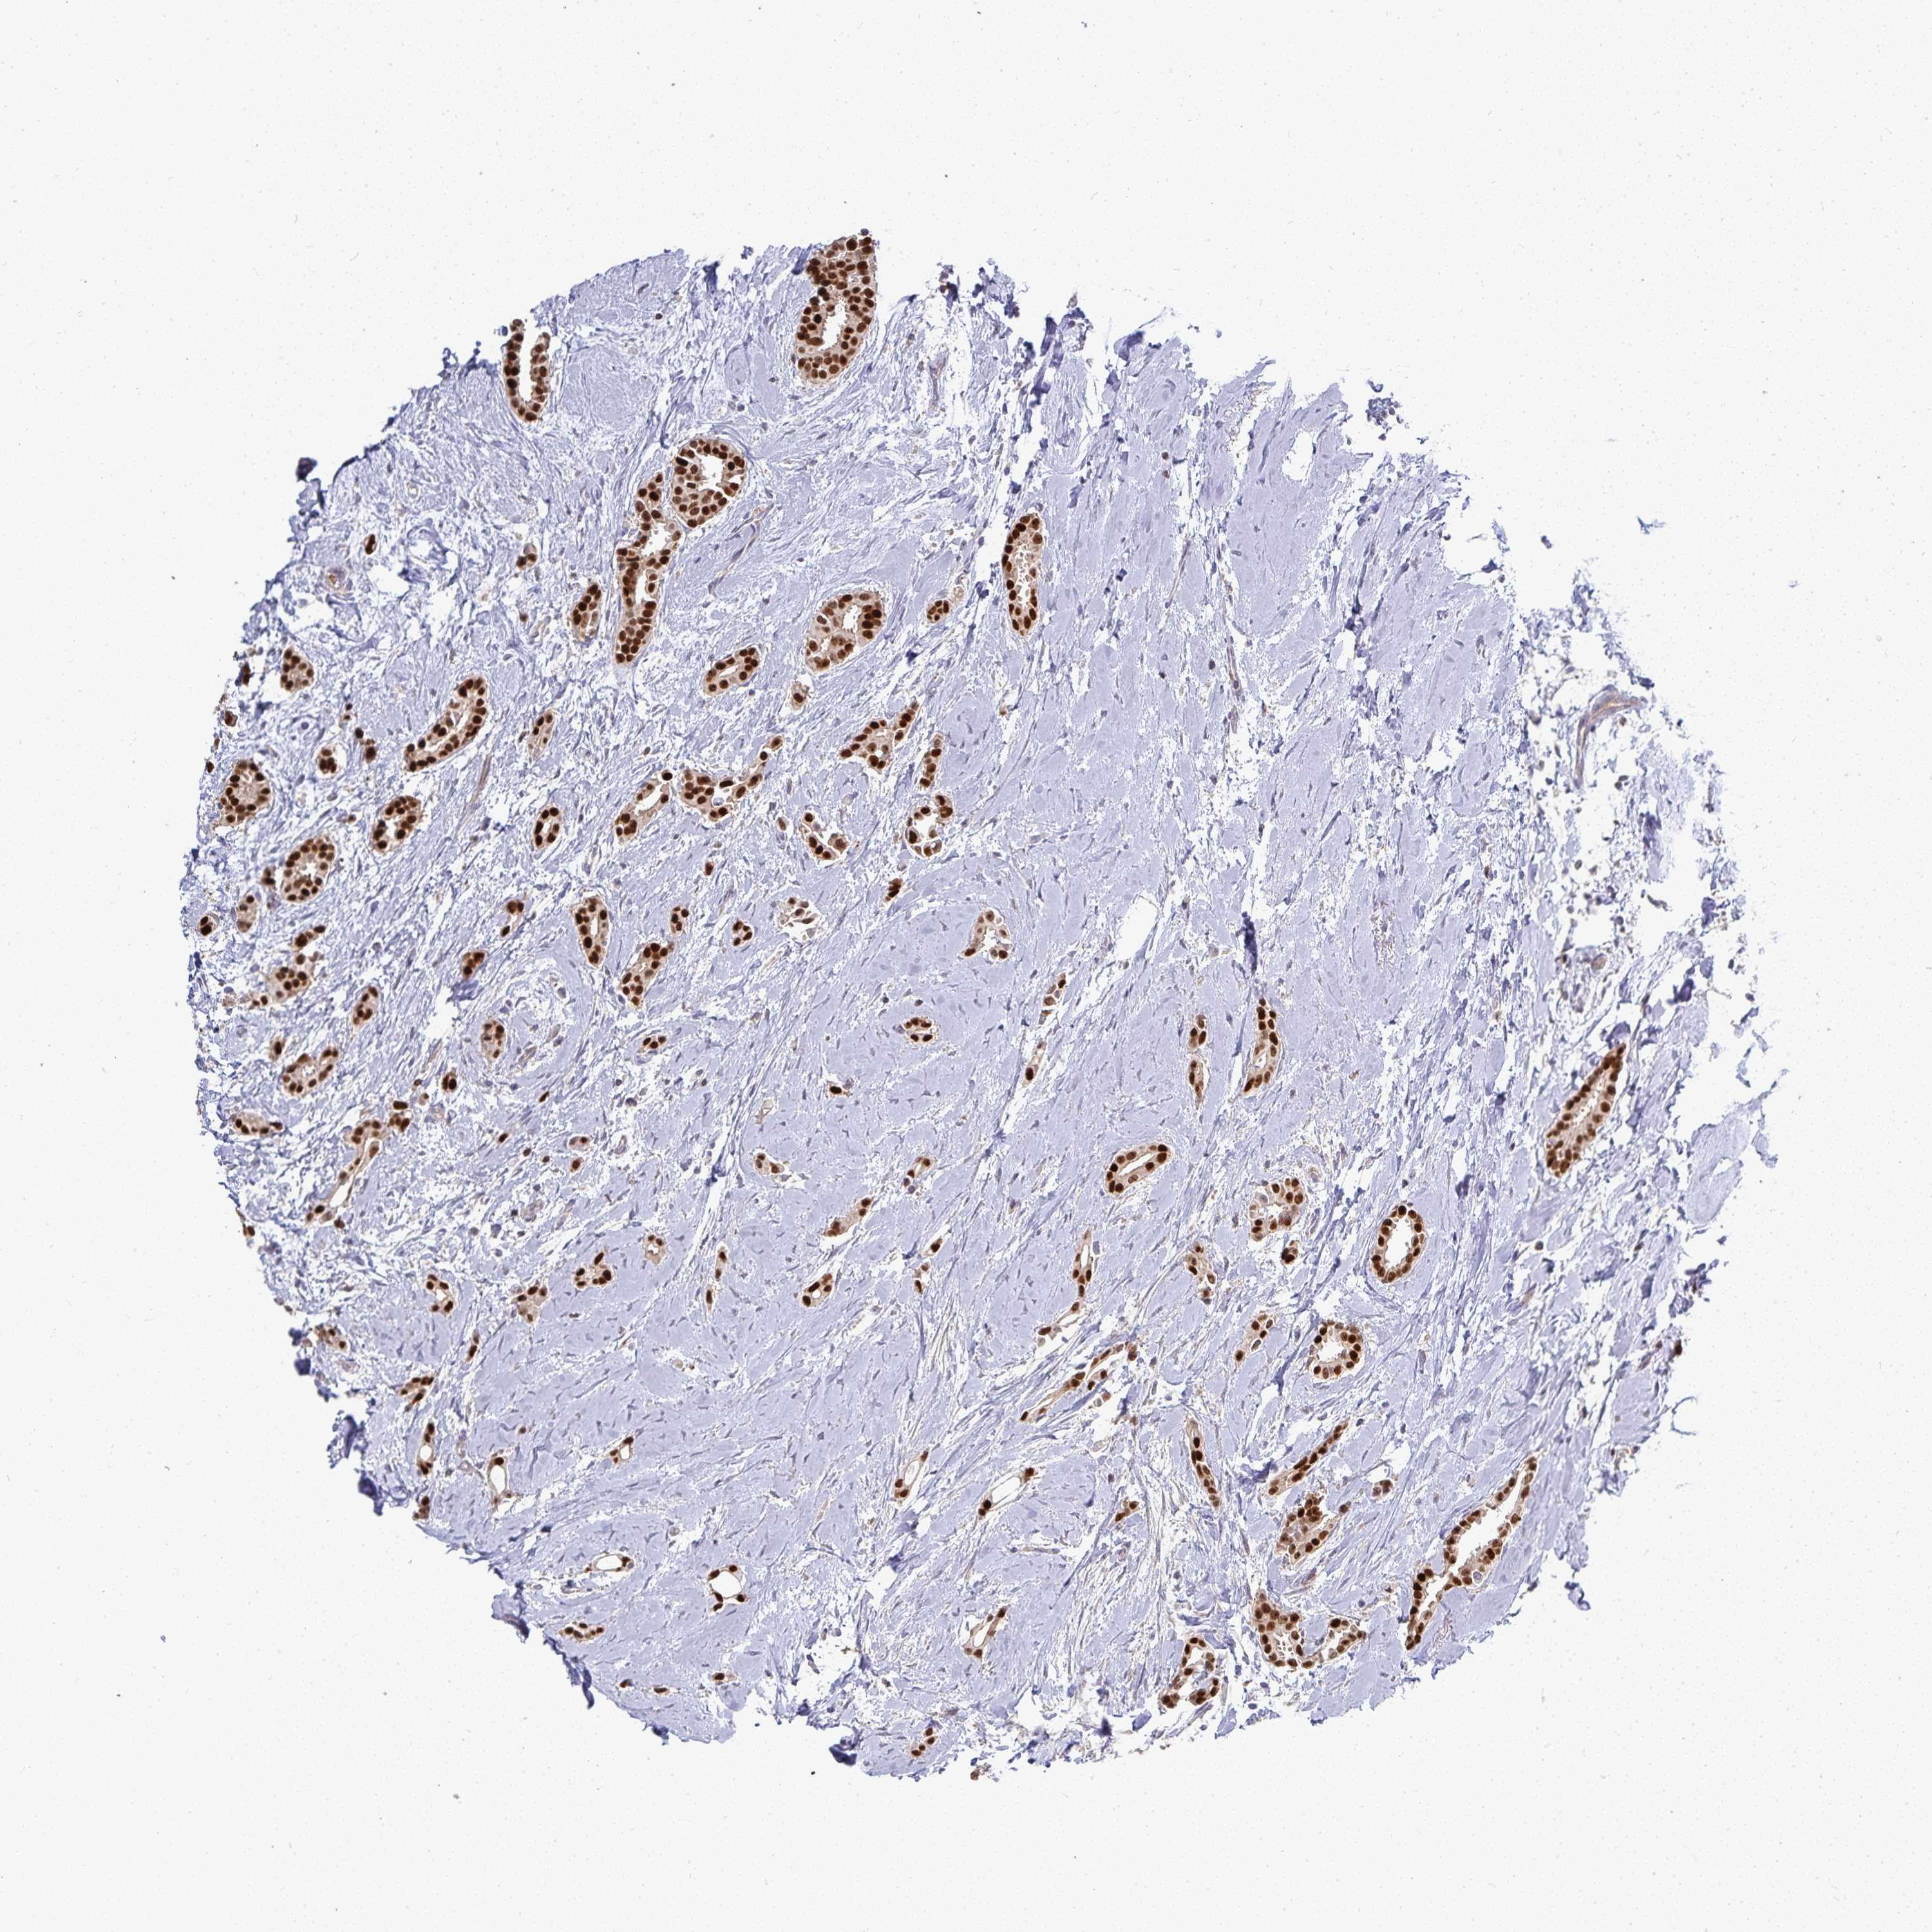

CANCER BREAST CANCER Show tissue menu

BRCA TCGA BRCA VALIDATION PROTEIN EXPRESSION